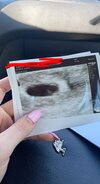

Hej!wczoraj byłam u lekarza 5+4 i widać zarodek i bijące serduszko! Kamień z serca

mimo plamien dzidzia się rozwija oby tak dalej